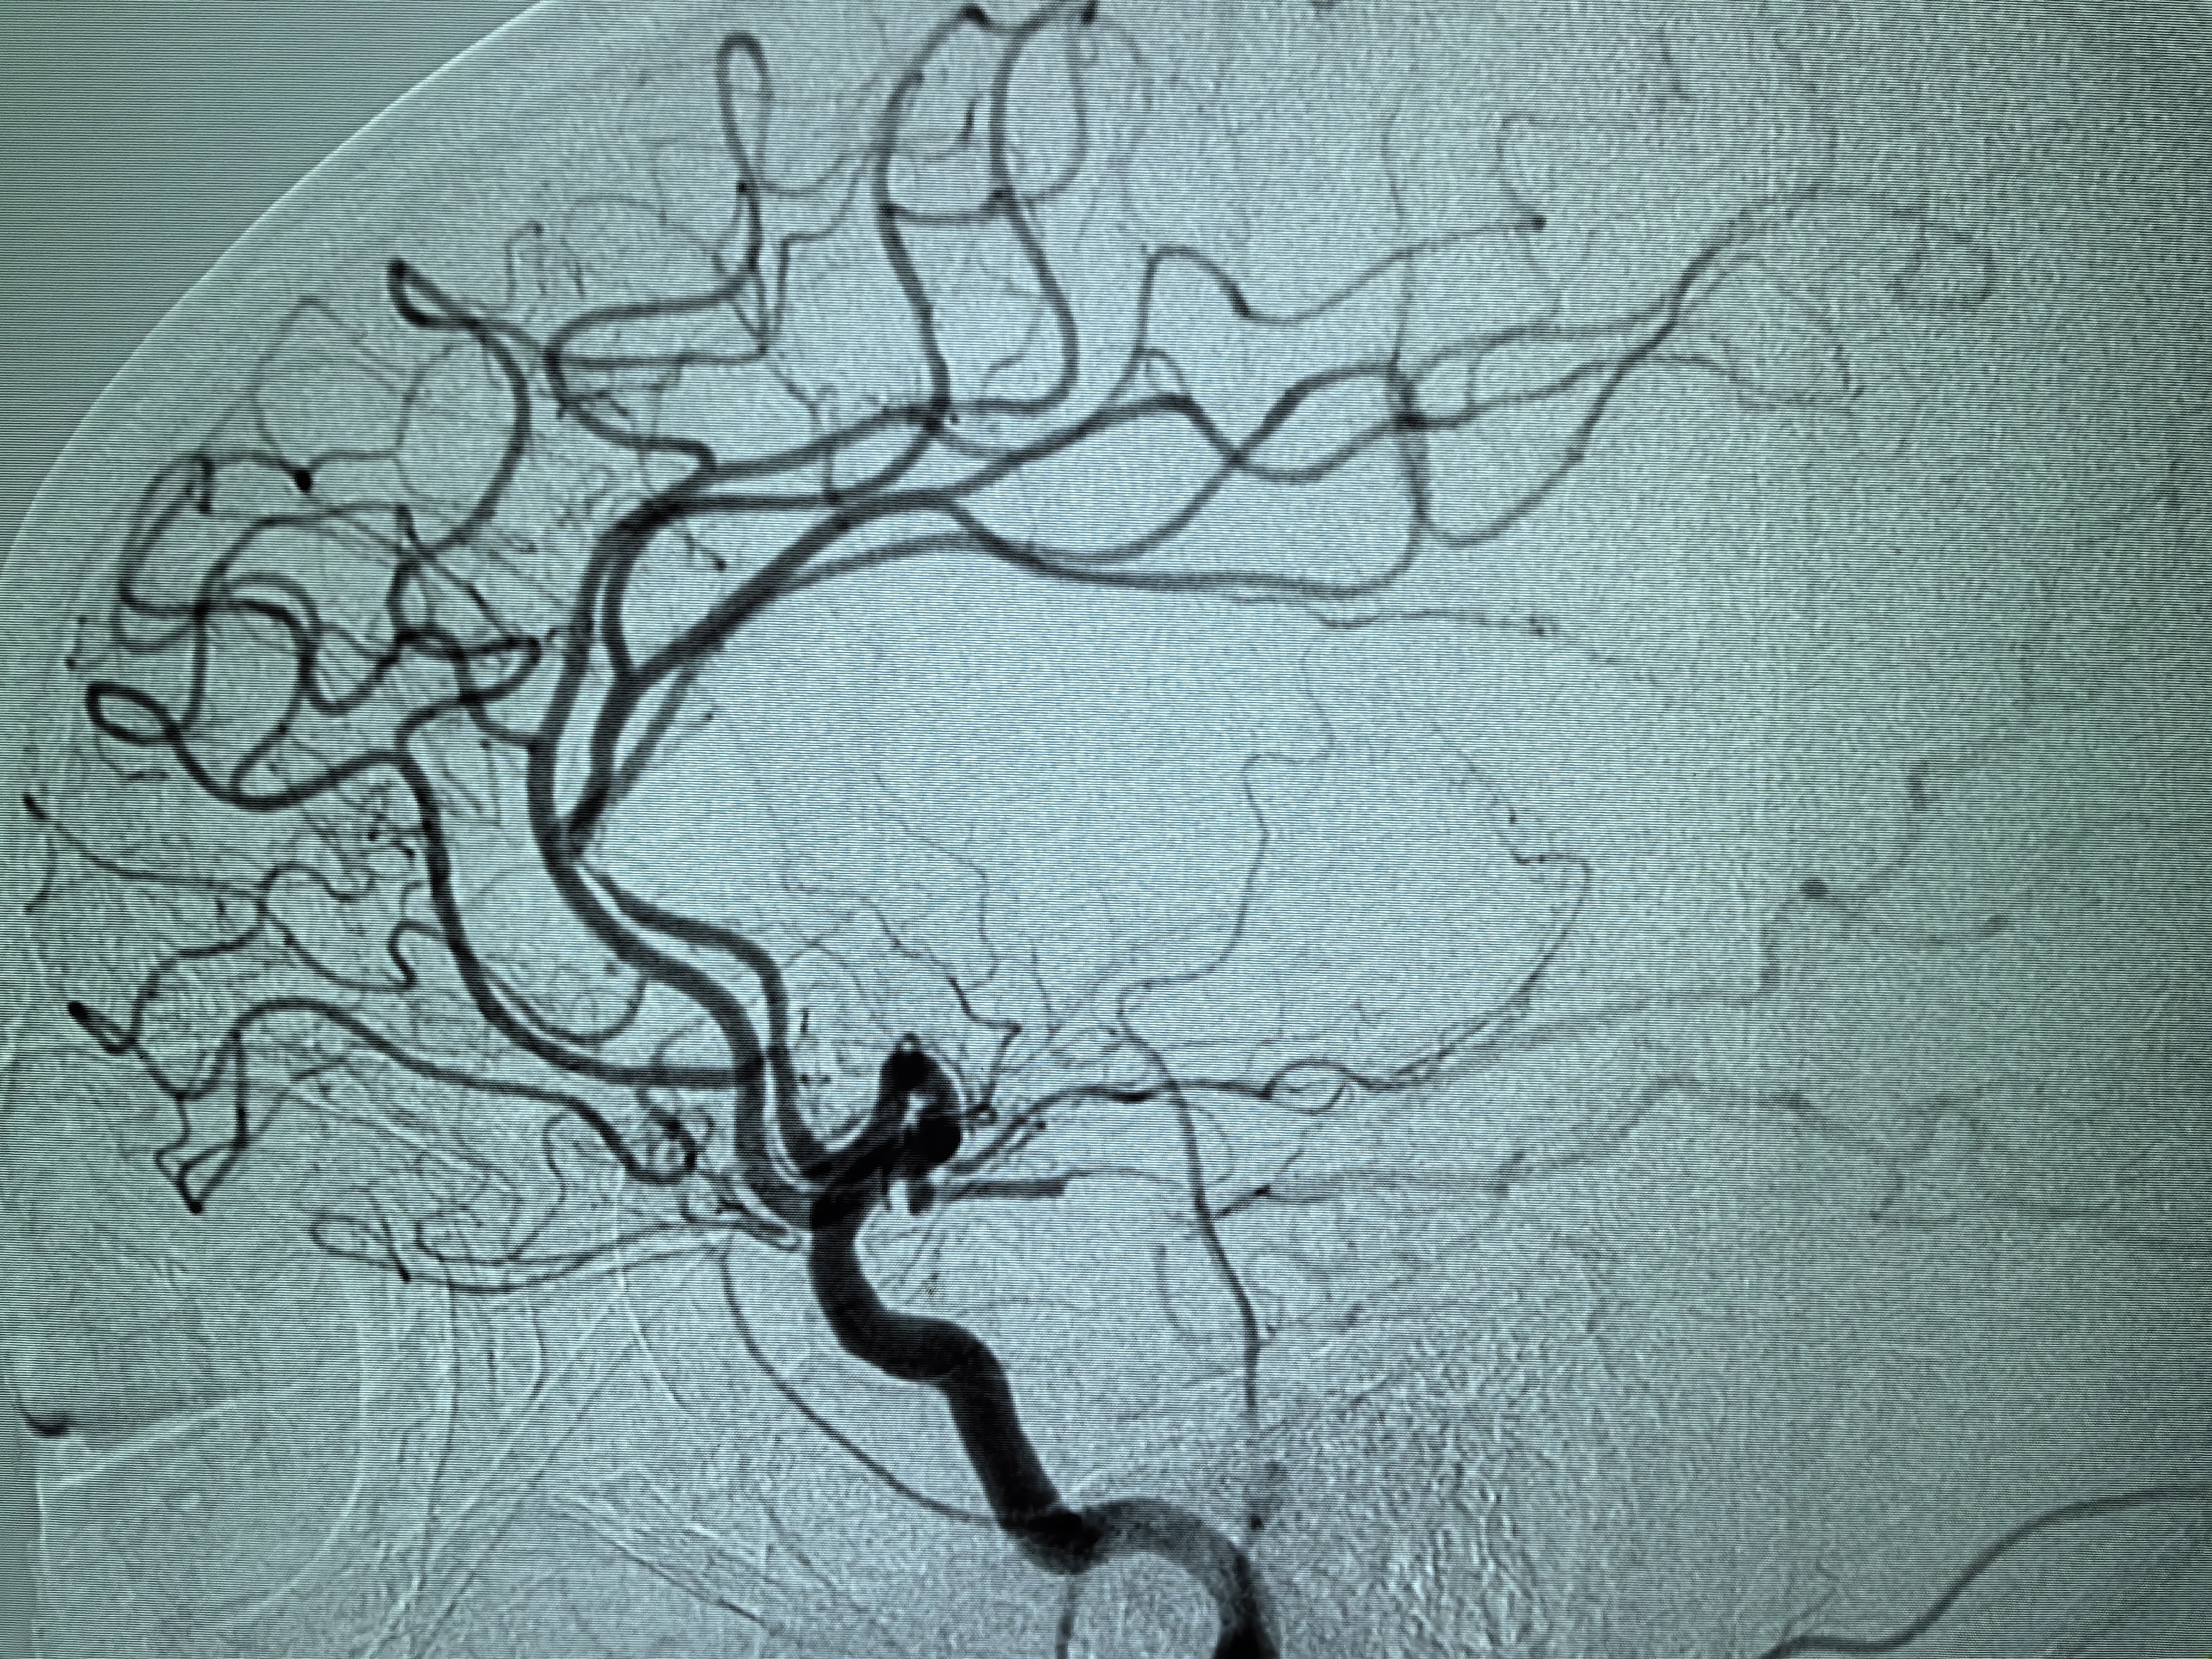

1、本例患者老年女性,系骨科术后次日醒后卒中,经核磁评估提示左侧大脑中动脉闭塞,系责任血管,患者心电图示房颤,考虑心源性栓塞可能性大。

2、本例患者SWIM技术取栓一次后血管再通,颅内血流通畅。